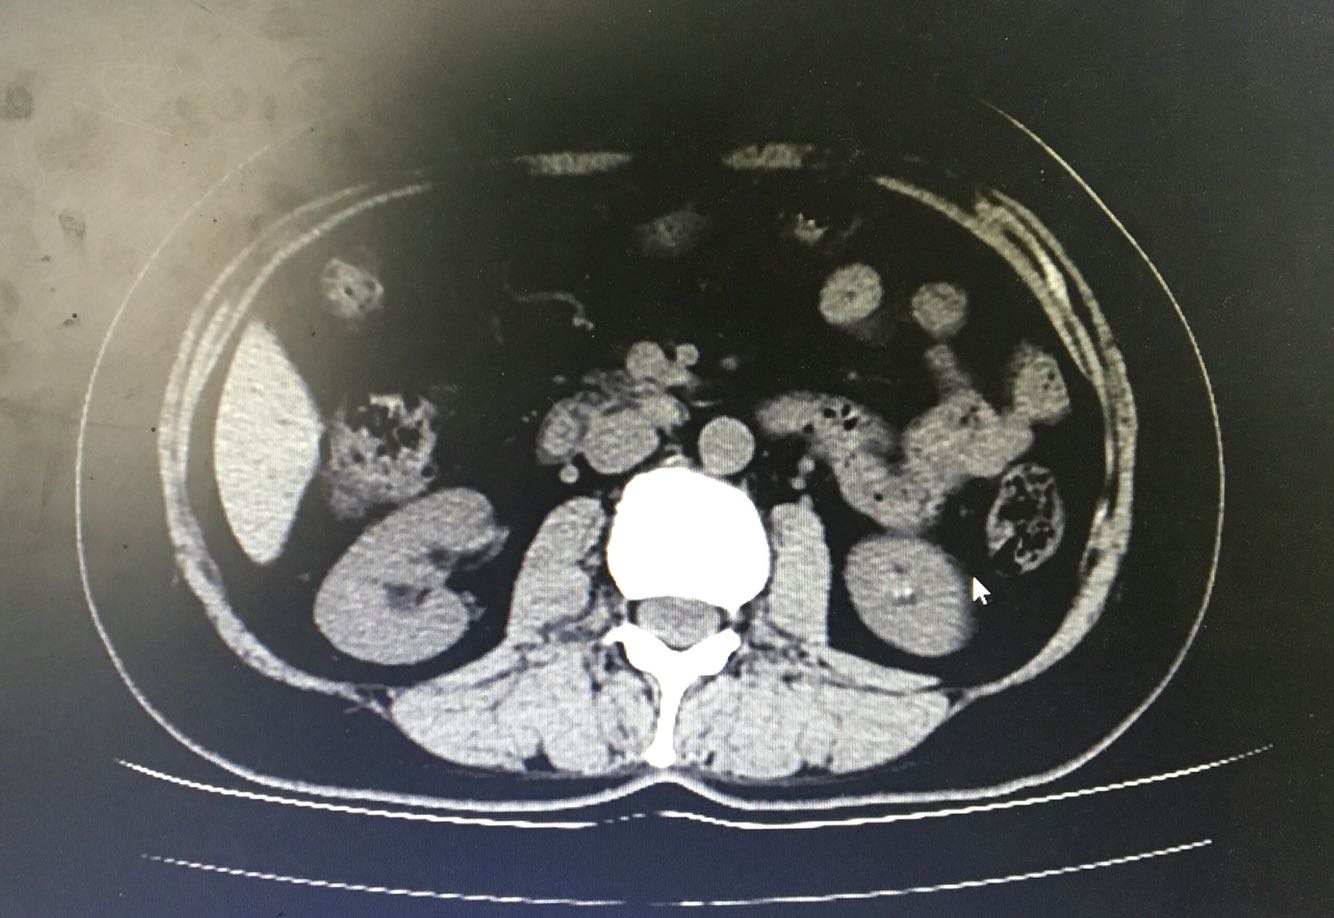

查体:神清,气平,BP:107/68mmHg,听力差,对答切题,双侧瞳孔等大等圆,直径3mm,对光反射存在,皮肤及巩膜无黄染,无贫血貌,浅表淋巴结未及肿大,颈软,气管居中,双肺呼吸音清,未及干湿罗音,心率90次/分,律齐,无杂音,腹平软压痛及反跳痛,未及明显肿块,肝肾叩击痛(-),移动性浊音阴性,双足背动脉搏动可及,双下肢无水肿,右足中趾红肿,神经系统检查(-) 辅助检查:血常规 HB99g/L,WBC2.7×10^9/L,RBC218×10^9/L, 免疫指标:IgA  <7mg/dl、IgG 2010mg/dl  IgM 50 mg/dl  叶酸:>24.8 ↑ng/ mL       维生素B12<50 ↓ pg/mL 甲状腺功能、肝肾功能、肿瘤指标、自身免疫指标、感染指标未见明显异常, 心脏超声:左房肥大 腹部B超:肝脏可见低密度病灶,左肾稍低密度灶,左肾盏可见小结石,余未见异常 盆腔CT:右下腹肠系膜多发小淋巴结显示,余未见异常